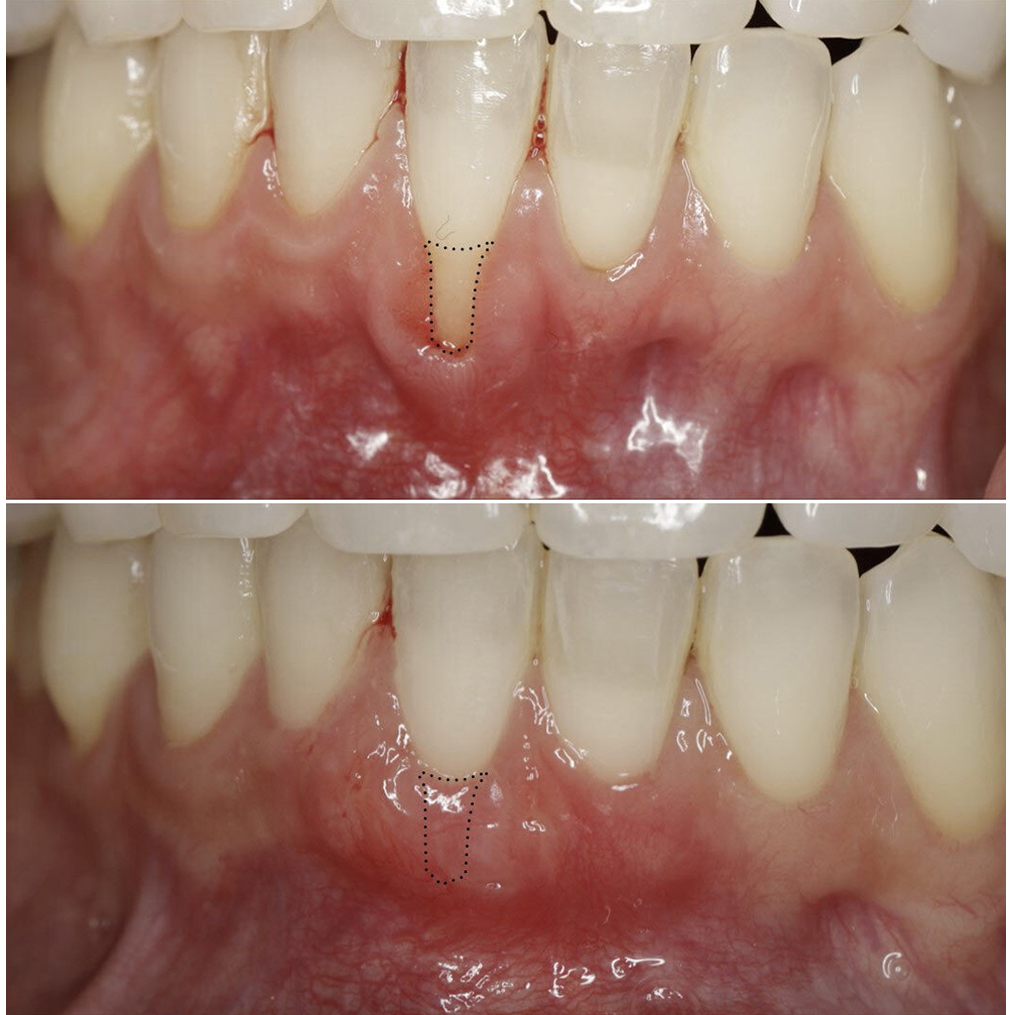

Young patient with severe recession on the upper teeth. Tissue from tissue bank (Alloderm) used to cover all the teeth in one visit

Young patient with recession on lower six front teeth. Tissue from tissue bank (Alloderm) used to cover lower teeth